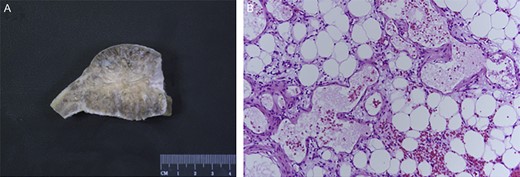

Histological evaluation revealed an admixture of mature adipose tissue and thin-walled blood vessels with no significant cytologic atypia (Fig. 3). The patient recovered well acutely in the hospital following surgical resection.

Gross (A) and microscopic specimens (B). The gross lesion was well demarcated and circumscribed. On microscopic analysis, multiple blood vessels were interspersed among the adipose tissue.